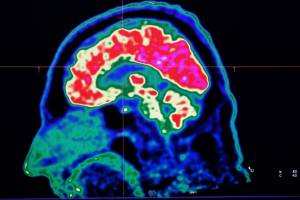

AFP/File / Fred TANNEAU A new study honed in on the brain circuitry responsible for upgrading or downgrading pain signals, likening the mechanism to how a home thermostat controls room temperature